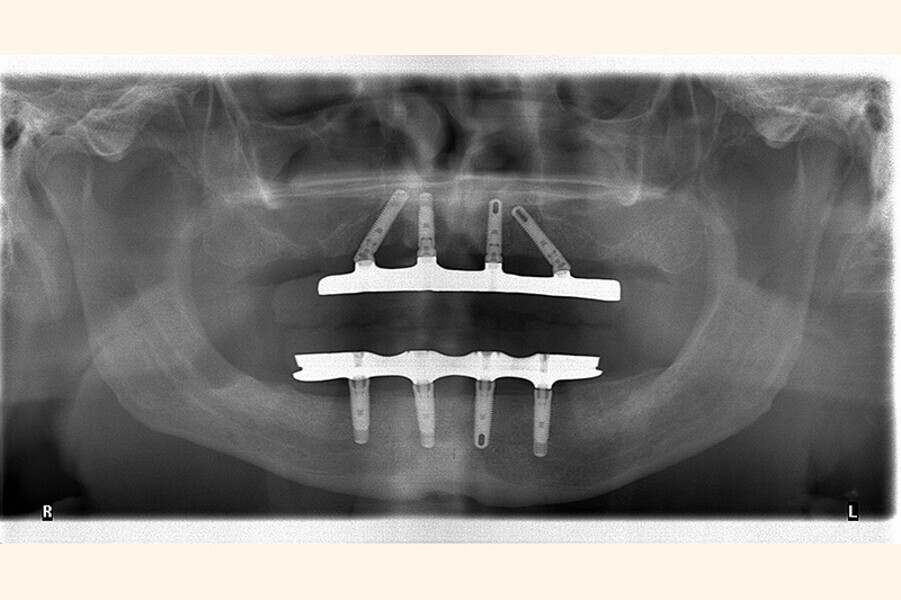

Fig. 4 Prótesis Híbrida inmediata y radiografía control con 6 años post-operatorio

Fig. 5. Prótesis Híbrida inmediata y radiografía control con 6 años post-operatorio

Fig. 6. Prótesis Híbrida inmediata y radiografía control con 6 años post-operatorio